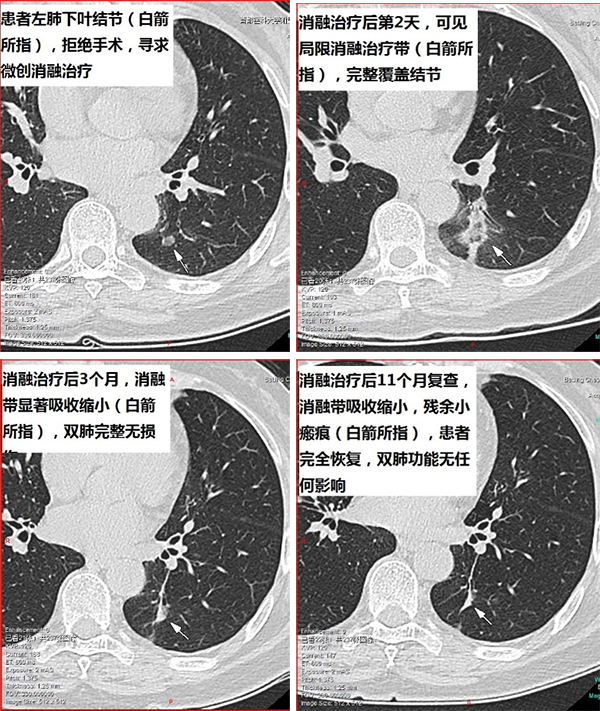

精准医疗,微创介入介入医学科是以影像引导的微创诊疗手术,专注于诊治各种疾病,致力于为患者提供安全、精准、高效的诊疗服务。科室依靠先进的CT等影像设备,通过微创技术手段开展肺结节、良恶性肿瘤等消融治疗,各部位穿刺活检及置管引流等,优势为不开刀、创伤小、恢复快、效果显著,提供契合现代医学“精准微创”理念的诊疗方案。一、微创消融治疗:肺结节、肺癌等病灶,可行微波/射频消融术及氩氦刀冷冻消融治疗,利用微创技术,不开刀,治疗肺结节及良恶性肿瘤等,肺结节、早期肺癌等可直接根治,达到与手术切除同等疗效,同时保留完整肺组织,不影响肺功能。中晚期患者可做到局部减瘤负荷联合全身靶向、免疫及放化疗等,双管齐下,效果优于单一治疗方案二、精准穿刺活检:利用微创穿刺技术直接取得病灶内部组织,…更多>>